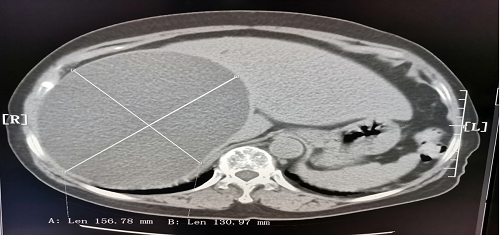

今日房縣網訊 11月28日上午,房縣人民醫院急診科主任雷禹接診的一位80歲高齡女性患者,其CT圖像顯示肝臟上長一14cmx15cm巨大囊腫. 且緊貼肝臟表面,有隨時破裂,引起大出血的風險,緊張的術前檢查中發現患者患有高血壓、血尿(+++)、白細胞增高等異常情況,需要進一步治療才具備手術條件,但不及時手術,又存在囊腫隨時破裂危及患者生命的巨大風險。

放射科主任楊光遠、中醫科醫師彭品在血管造影機監視下,采用局部麻醉,用一根直徑不到1毫米的細針,直接經皮膚穿刺到肝臟囊腫內,緩慢抽出淡黃色液體約1350ml. 手術用時2小時30分鐘,患者癥狀漸漸改善。13:30患者肝臟上的這顆定時炸彈被折除,患者被安全送回病房。介入室護理況娟、保障手術安全的手術室醫生楊垚均堅守到安全送走患者。